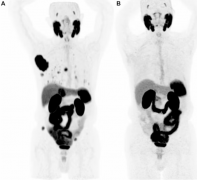

超声 CT MRI 核医学影像 PSMA-PET 研究人员报道,前列腺特异性膜抗原(PSMA)-PET显像有望成为可视化肝细胞癌患者治疗反应的工具。 第一作者Ajith Antony, MD,明尼苏达州罗切斯特市梅奥诊所(Mayo Clinic)的MD及其同事指出,在对接受局部区域治疗或免疫检查...